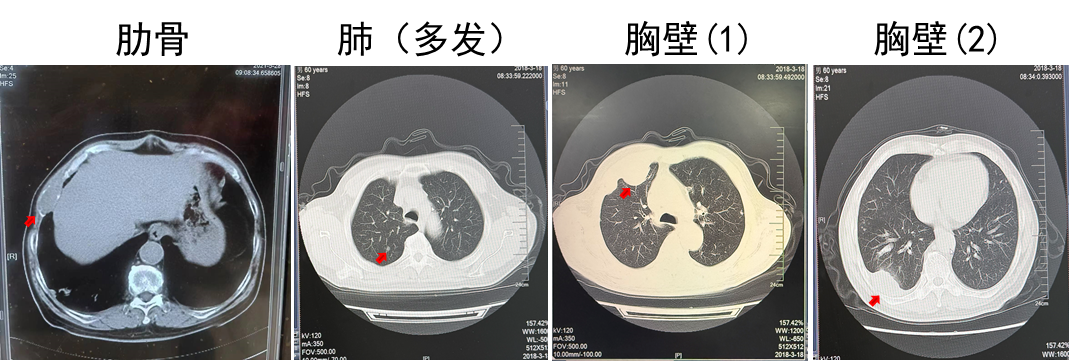

2018.03 PET-CT提示多发肺转移,肋骨转移

2018.03.22胸壁穿刺显示转移性癌,考虑肾来源

诊断为T2N0M1,IV期,IMDC低危

2018.03.22舒尼替尼50 mg QD。肋骨肿瘤注射唑来膦酸3周1次(共3次),同步放疗3 Gy(共10次)。

疗效:肋骨病灶疾病稳定(2年),肺部病灶部分缓解(2年)。

(舒尼替尼单药联合放疗,肋骨病灶实现SD)

(舒尼替尼单药联合放疗,肺转移病灶实现PR)

该例患者诊断为左肾透明细胞癌,T2N0M0,术后5.5年复发,伴肋骨转移、肺转移和胸壁转移。结合循证医学证据及中国临床肿瘤学会(CSCO)肾癌诊疗指南对低危患者推荐,优先使用舒尼替尼进行一线治疗,患者出现不耐受情况,调整剂量后肺部病灶获得部分缓解,肋骨病灶疾病稳定,PFS 2年。后续进展可考虑其他治疗方案。